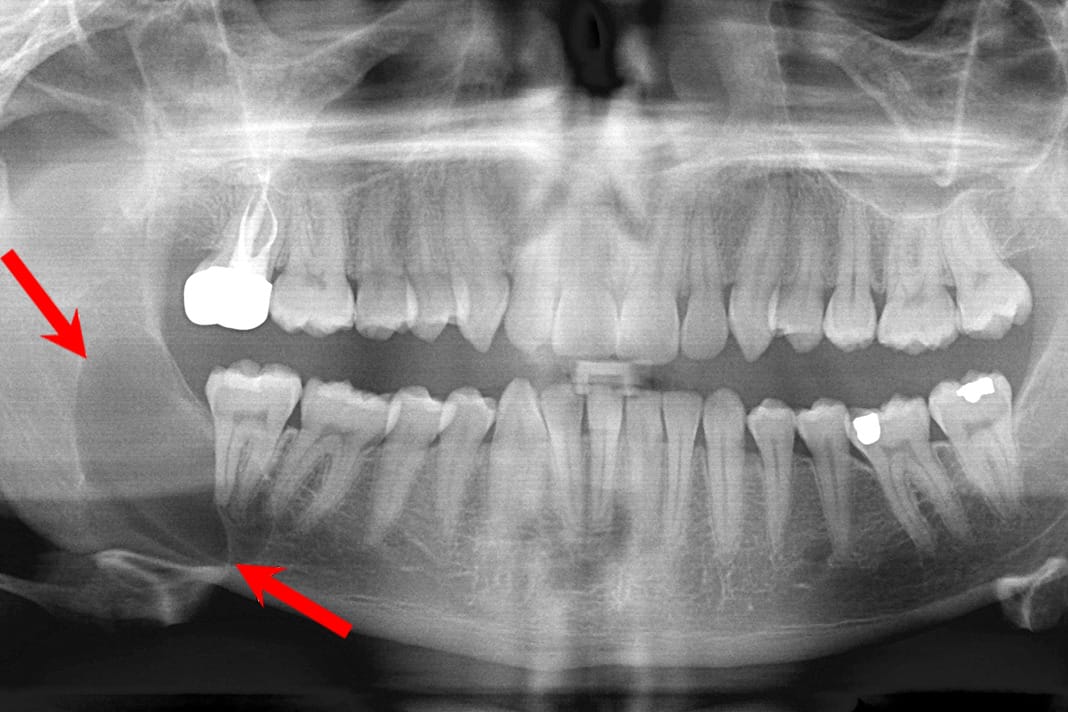

Dentigerous cyst: Generally asymptomatic, this cyst is the second most common cyst occurring around the crown of an impacted tooth, unerupted tooth, supernumerary tooth, or odontoma. Therefore, it is not unexpected to see this cyst around the impacted third molars of young adults. This cyst appears well-circumscribed on a radiograph. To treat this cyst, tooth extraction and excisional removal of the cyst proved to have an excellent prognosis, although the area must be evaluated regularly for ameloblastoma.1 (see Image 6)

Image courtesy JawCyst.jpg: Coronation Dental Specialty Group [1]derivative work: Jbarta and Mikael Häggström (CC BY 3.0 via Wikimedia Commons)

Courtesy Coronation Dental Specialty Group (CC BY 3.0 via Wikimedia Commons)